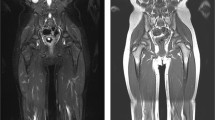

Extensions to the core protocol should be implemented in high-risk populations (Table 4). These may include sagittal imaging of the whole spine, dedicated brain imaging, MRI mammography, and coverage of the lower limbs. Of note, the administration of CA may be required in subjects with cancer predisposition syndromes (e.g. Li–Fraumeni syndrome) for better assessment of specific body regions (e.g. brain) (Fig. 2).

Extensions to the core protocol. This picture summarizes possible complements to the core protocol. When assessment of the spine is required, sagittal short tau inversion recovery (STIR) is used. In subjects with a high risk of vertebral tumours, a sagittal T1 weighted turbo spin echo (TSE) sequence can be additionally performed. When the WB-MRI protocol includes the lower limbs, such as in subjects with Li Fraumeni syndrome, all sequences in the core protocol are extended to the feet. When there is an increased risk of central nervous system (CNS) tumours, a dedicated brain sub-protocol is performed, with multiple sequences and with contrast administration (+ c). In subjects with a low risk of CNS tumours, the assessment of the brain can be improved with a short brain protocol, including fluid attenuated inversion recovery (FLAIR) sequences. Single breath-hold T1 weighted gradient recalled echo (GRE) sequences can be performed for the assessment of the lungs. In subjects with neurofibromatosis, the STIR sequence should be performed in either the axial or the coronal plane, covering from neck to feet, for facilitating the detection of peripheral nerve sheath tumours (arrows)